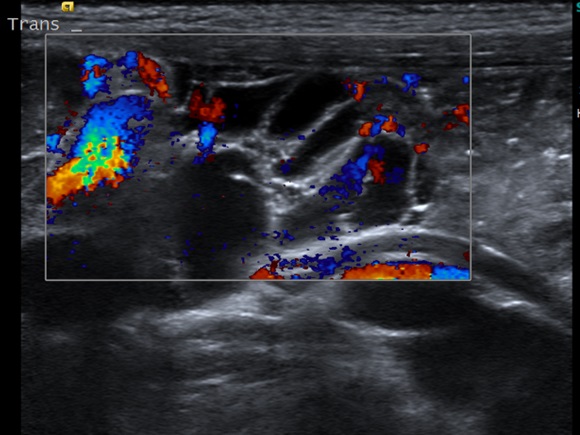

A los 7 años vuelven a consulta con el calendario, llama la atención que el dolor es diario y en la misma localización. Se vuelve a interrogar sobre el dolor y el paciente se señala con la punta del dedo una zona bien delimitada en hipogastrio. Se orienta como un síntoma de alerta, por lo que se decide realizar una ecografía clínica que muestra una estructura quística, poliseptada en línea media por debajo del ombligo de 3,5 x 1,9 x 3 cm con vascularización presente en pared (Figura 1). Ante la sospecha de una masa abdominal, se contacta con el hospital de referencia y es diagnosticado de una malformación linfática intestinal.

Figura 1. Ecografía abdominal con estructura quística, poliseptada en línea media por debajo del ombligo de 3,5 x 1,9 x 3 cm con vascularización presente en pared orientada como malformación linfática abdominal